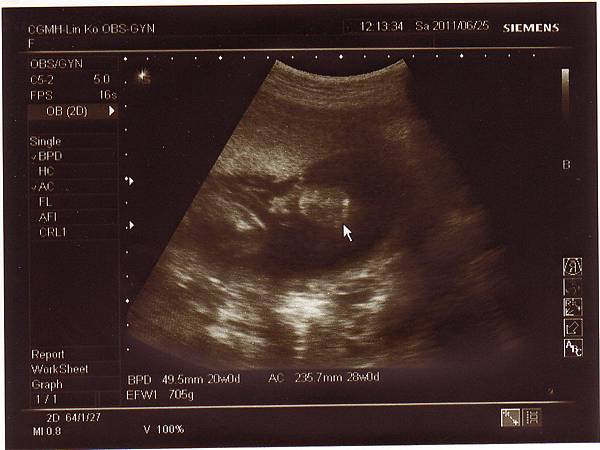

2011.06.25 當天先去超音波室做了仔細的超音波檢查,

檢查心臟.是否兔唇.手腳.肺動脈....等等,

一切都非常正常,也確定是個兔女郎!

只是後來到診間時,醫生聽寶寶心跳有幾秒是比較慢的,